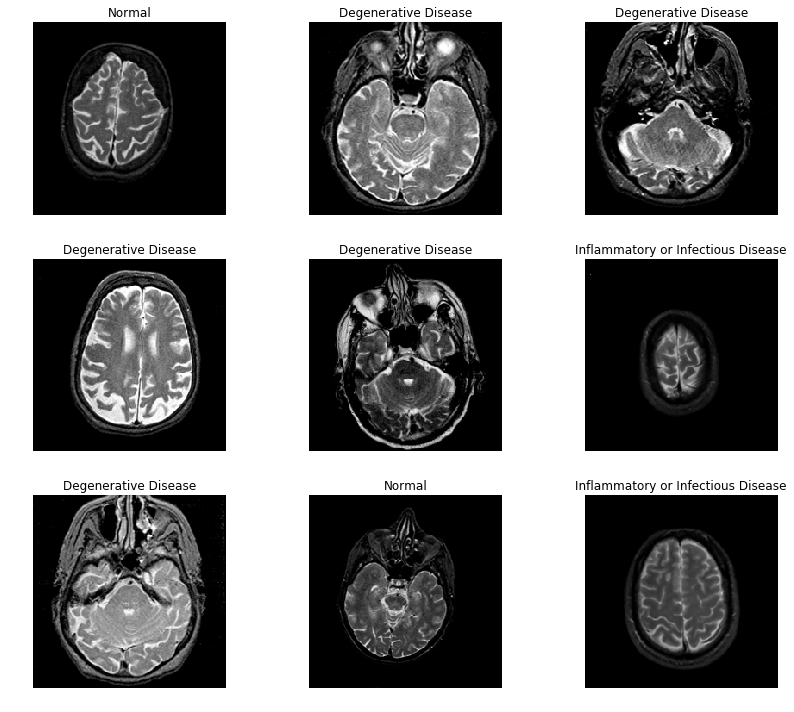

In this paper, we have published a dataset consisting of 5285 T1-weighted MRI images belonging to 37 categories in collaboration with the National Insitute of Neuroscience & Hospitals (NINS) of Bangladesh. Besides that, we have used two other public datasets, the School of Biomedical Engineering brain MRI dataset that comprises 3064 T1-weighted contrast-enhanced images of 233 study patients indicated in TableII [39]. The second dataset is the Harvard Medical School Whole Brain Atlas brain MRI benchmark [8] that consists of 1133 T2-weighted brain MRI images of 38 patients shown in Table III. The size of all images is 256x256 pixels in the axial plane.

Refer to caption

Figure 5: Sample Harvard Whole Brain MRI Dataset

The School of Biomedical Engineering, Southern Medical University brain MRI dataset comprises of three classes of brain tumors, Meningioma, Glioma, and Pituitary tumor, as depicted in Table II [39]. The Harvard Medical School dataset entails five classes, Cerebrovascular class (stroke), Neoplastic, Degenerative, and Inflammatory disease, as shown in Table III. We have used a 5-fold cross-validation technique to perform the network re-training, which ensures that we overcome the size limit of our dataset without over-fitting.